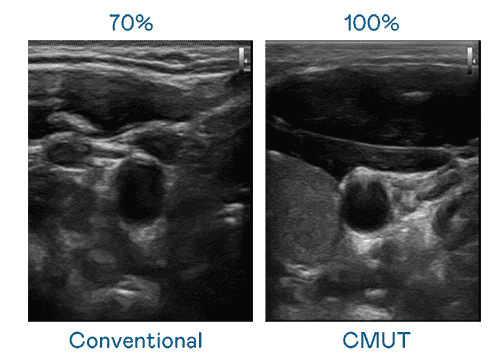

CMUT 技术是一种用电容式微机电元件来产生超音波讯号的技术。。。与传统 PZT 压电式技术相比,,,CMUT 频宽增加 30%,,,,更宽频的超音波讯号让影像解析度大幅提升,,是实现高影像品质医疗超音波扫描、、、促进精准医疗发展的关键技术。。。。

大频宽带来超清晰影像

超音波影像的解析度高低,,,,首先取决于探头能发出的讯号频宽。。。。z6尊龙 CMUT 可提供高清晰的超音波讯号,,,提供高频宽、、、、高灵敏度、、、影像纹理细节更高的超音波影像,,协助医护人员缩短影像判读时间及利用精准的医疗影像进行诊断。。。。